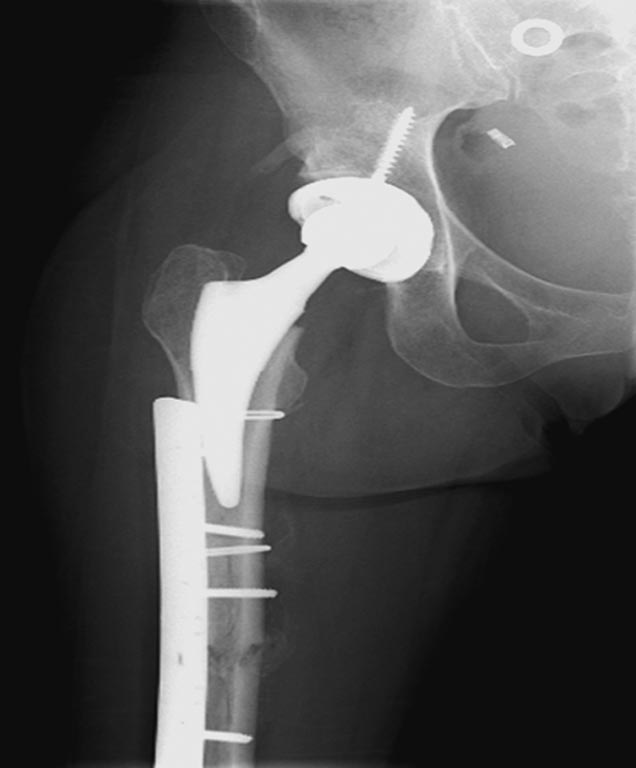

На 25 день с момента травмы операция на Jackson table с боковым обширным

доступом. Удаление стержней с местной обработкой. В тазобедренном

суставе удаление головки, на дне вертлужной впадины полная отслойка

хряща. Вертлужный компонент с одним винтом и короткая ножка -  Fitmore

Выписана. Нагрузку разрешили на левой стороне, а полная в 3 мес.  Здесь

снимки при амбулаторном наблюдении​: послеоперационно, 2 мес, 3 мес и 6

мес. Нагрузка полная, отсутствует хромота, и нет жалоб.